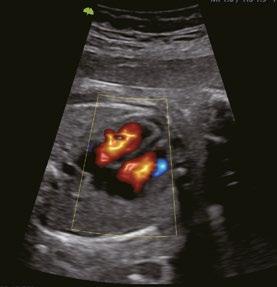

Fetales Herz VLuminous Flow

Eine innovative Technologie, die die Visualisierung des Blutflusses verbessert, indem sie eine 3D-Darstellung der Farb-/Power-Doppler-Bildgebung anzeigt.